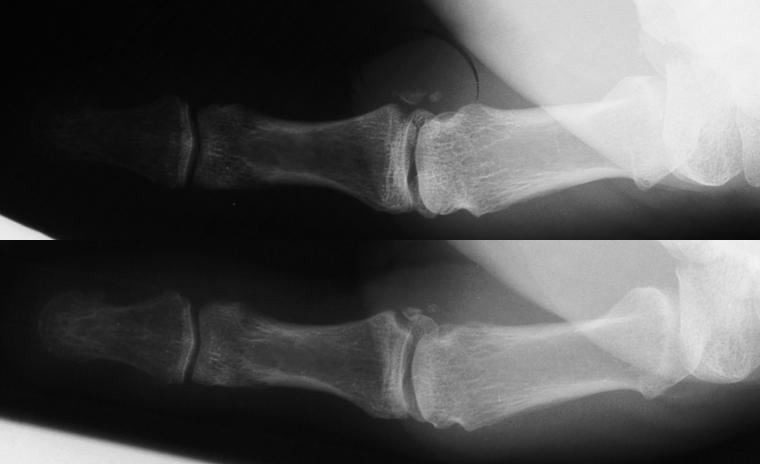

Not all need repair. This patient had an injury associated with rotation of the avulsion fracture. This often indicates a combination of fracture and ligament tear. However, the joint was stable, and had a good result from splinting alone. The bottom film shows the expected asymptomatic fibrous nonunion.

Click for larger image